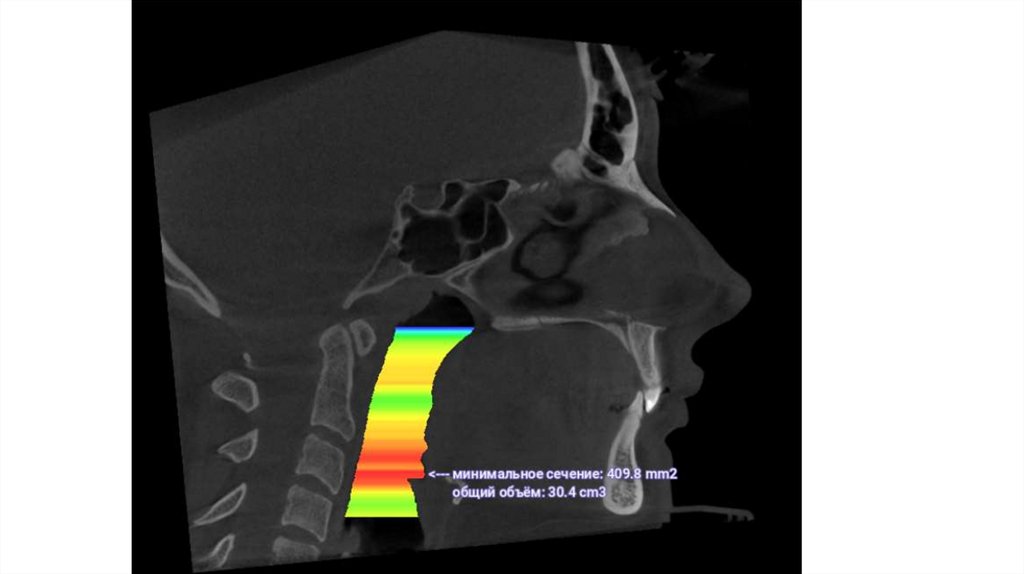

• Корни верхних моляров в пазухе (= невозможно двигать

зубы назад)

• Недостаточная толщина кости в зоне имплантации

нижних зубов